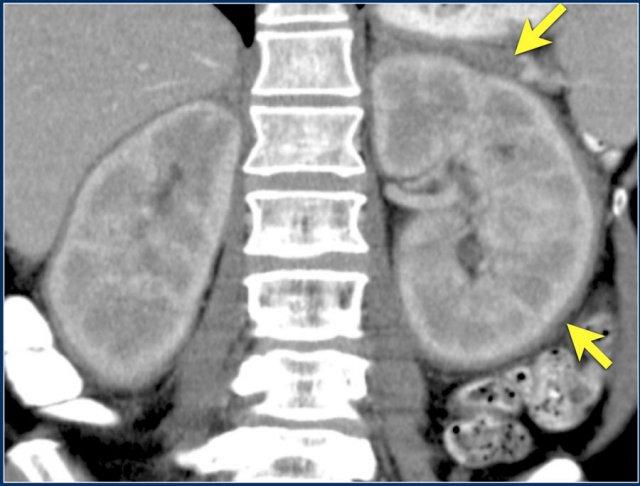

Hình ảnh cho thấy bệnh nhân có nhiều tổn thương di căn thận.

Lưu ý huyết khối khối u trong tĩnh mạch thận trái.

Đây là hình ảnh của một bệnh nhân ung thư phổi.

Có một tổn thương di căn ở thận trái và nhiều tổn thương di căn hạch bạch huyết (mũi tên).

Nếu đây là biểu hiện duy nhất, sẽ rất khó để phân biệt với ung thư biểu mô tế bào thận có di căn hạch bạch huyết.